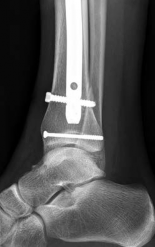

Once reduced, the articular block is secured with independent 3.5 mm or 4.0 mm partially threaded cancellous lag screws. These screws must be placed strategically—typically in the anterior or posterior half of the epiphysis—to leave the central medullary canal completely unobstructed for the nail.

Image

Fibular Fixation Strategy

The role of fibular fixation in distal tibia fractures remains a topic of academic debate, but in the context of intramedullary nailing, it is often a highly valuable adjunct. Plating the fibula restores the length of the lateral column and corrects rotational malalignment, effectively converting a highly unstable distal tibia fracture into a more manageable, length-stable pattern.

Fibular fixation is typically performed prior to tibial nailing. An open reduction and internal fixation utilizing a one-third tubular plate or anatomic distal fibula plate is standard. By stabilizing the fibula, the tendency for the distal tibia to drift into valgus during nail insertion is significantly mitigated.